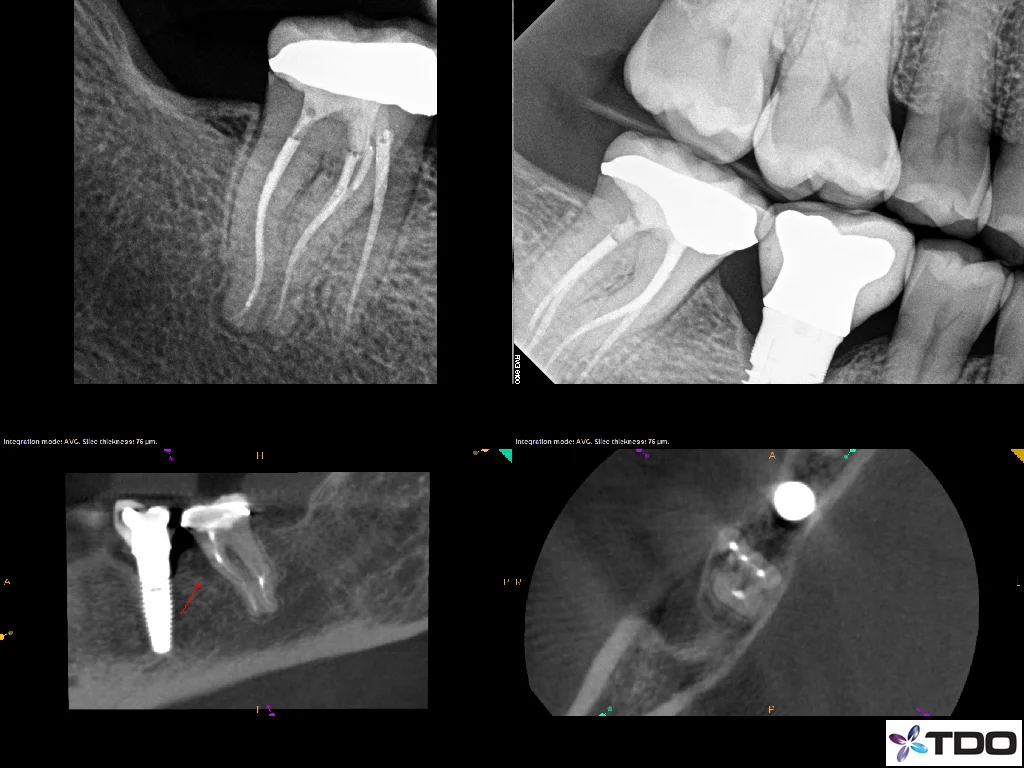

Cone Beam Computed Tomography (CBCT):

Historically, we have had to rely exclusively on 2-D radiographs to evaluate patients. While this has been and continues to be adequate in most cases the Cone Beam Computed Tomography gives us the ability to literally evaluate the teeth and surrounding tissue in 3 dimensions. This is invaluable, especially when treating the difficult cases seen in a specialist's office. These high resolution images can be obtained quickly in our office and are achievable with very low radiation to the patient. We primarily utilize this technology to investigate canal location, understand root morphology, identify periapical changes not visible on traditional radiographs, and to plan for surgery.